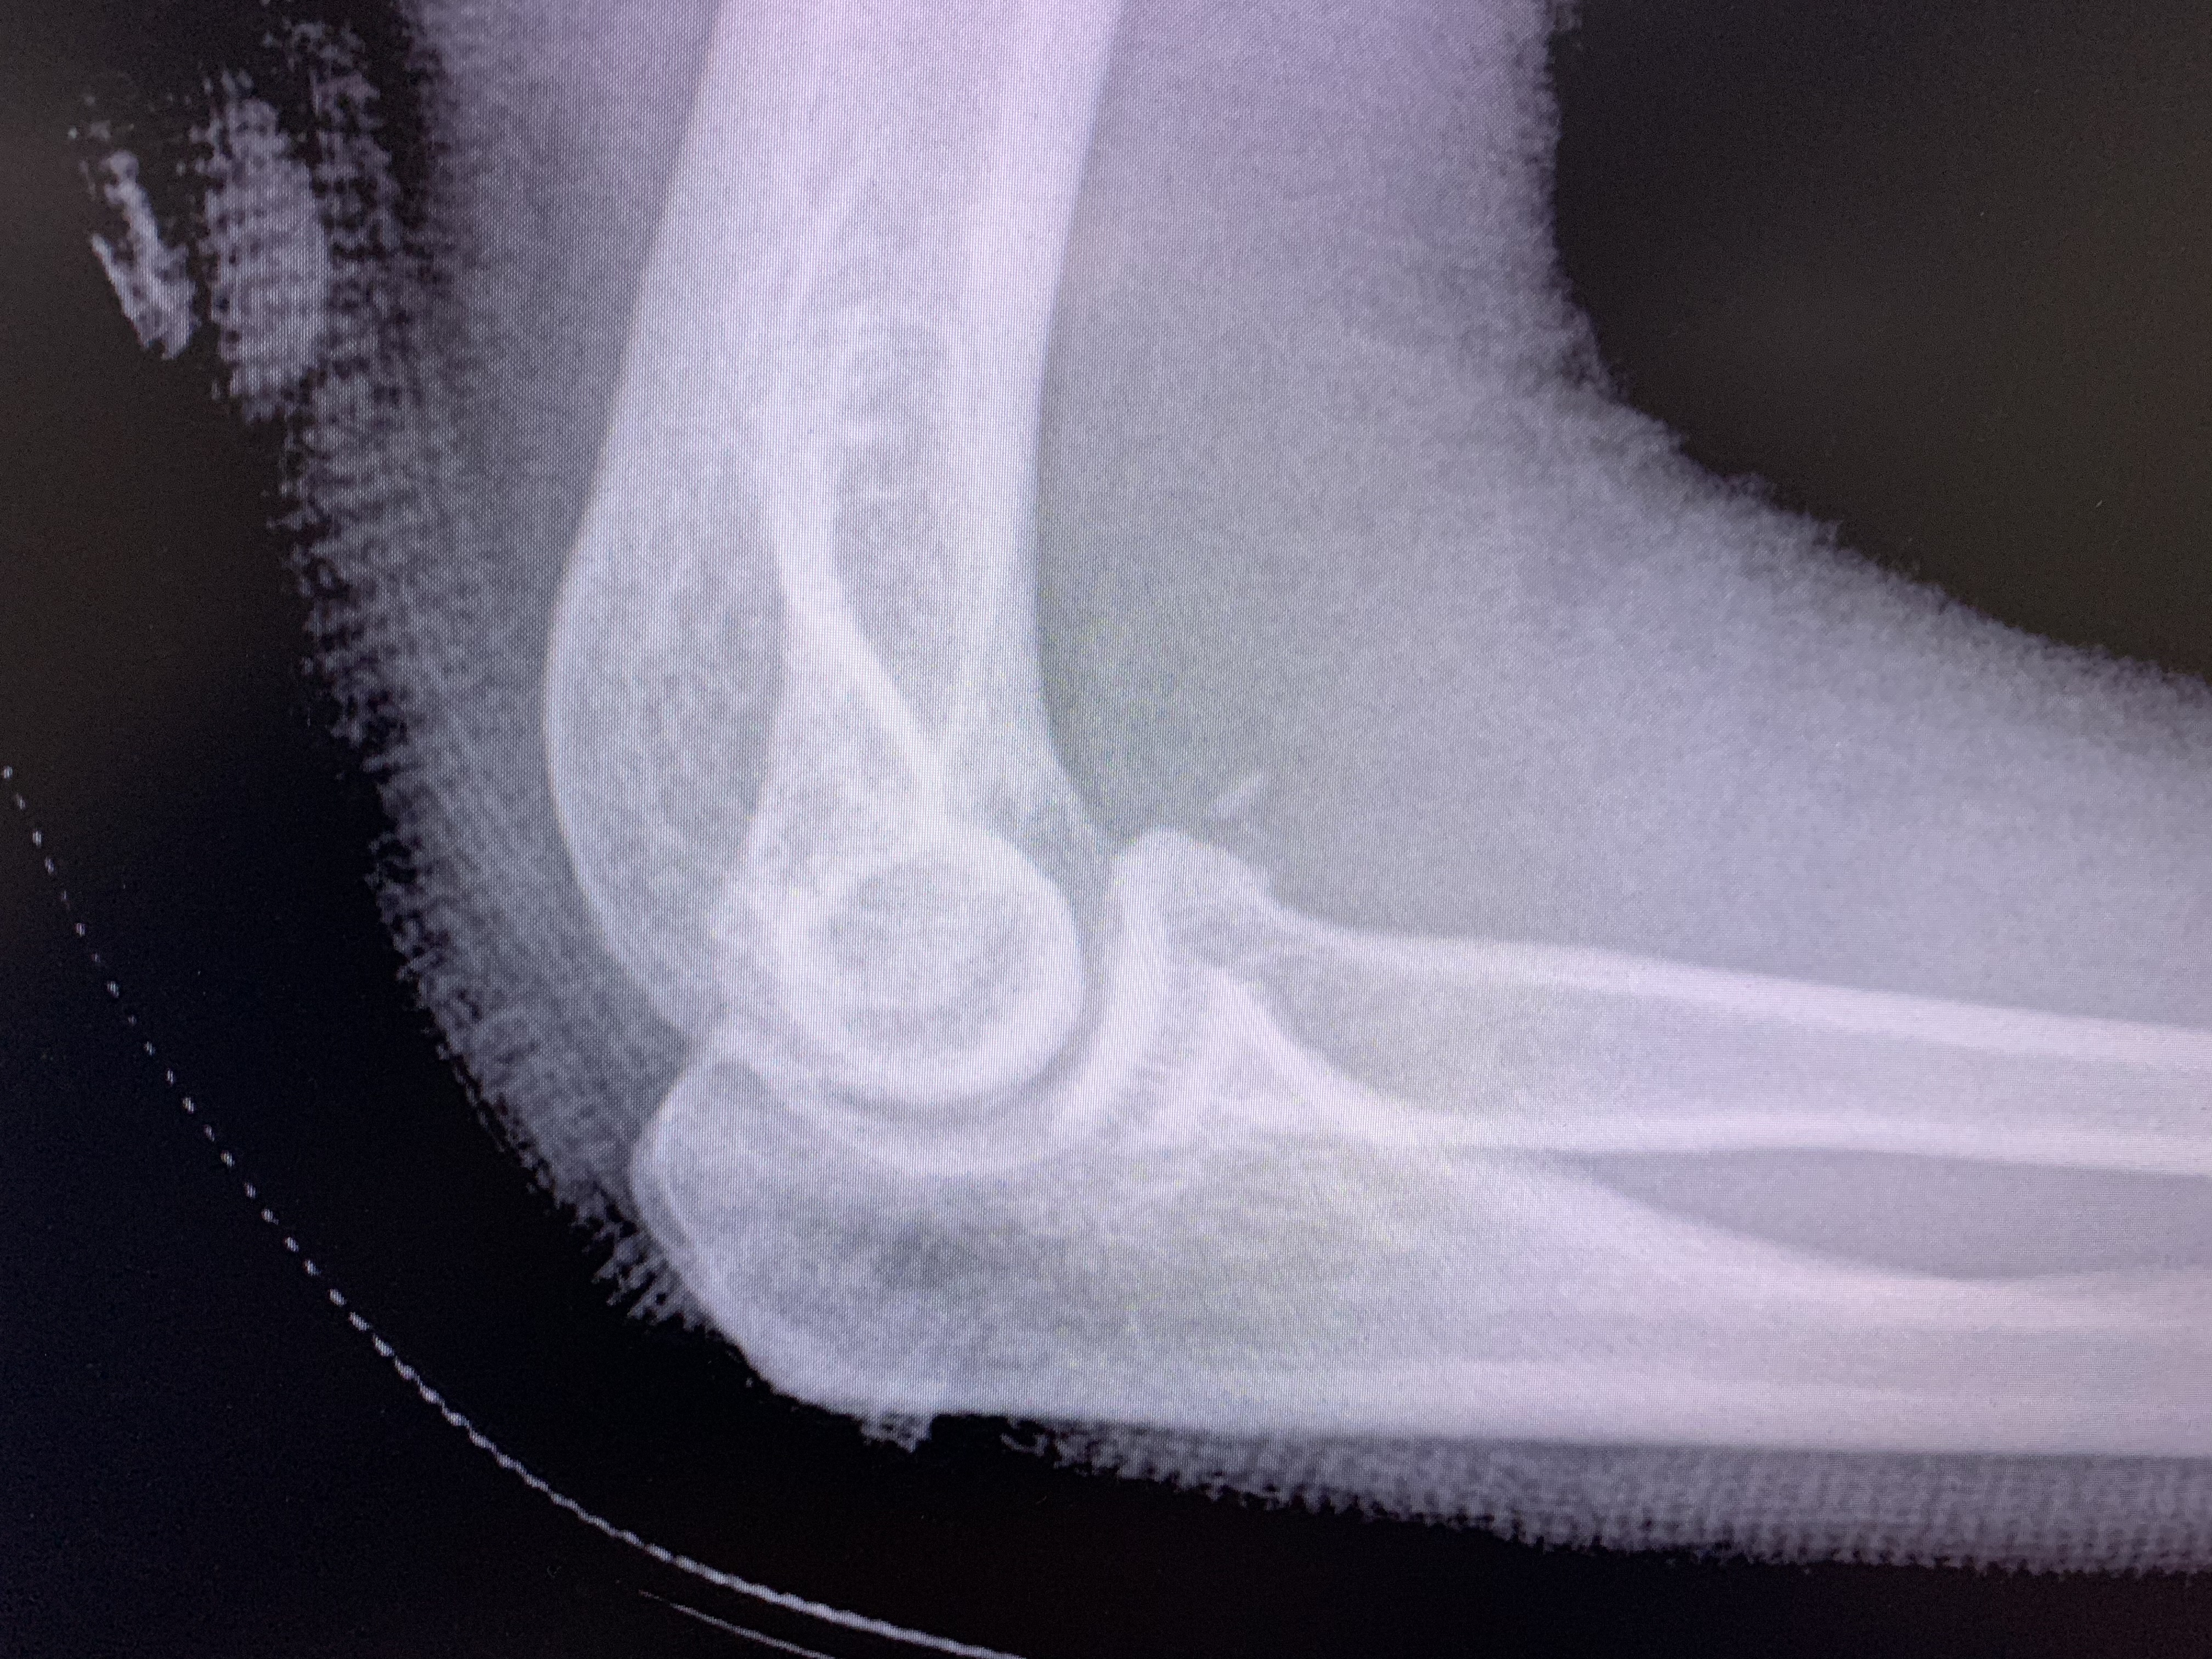

Galería de fotos clínica, servicios, cirugías, casos de pacientes Visítenos, ambiente limpio, agradable y seguro. Trabajando Operando en tiempos de coronavirus Dr Barquero Traumatologo Compartir en X (Se abre en una ventana nueva) X Comparte en Facebook (Se abre en una ventana nueva) Facebook Imprimir (Se abre en una ventana nueva) Imprimir Compartir en WhatsApp (Se abre en una ventana nueva) WhatsApp Enviar un enlace a un amigo por correo electrónico (Se abre en una ventana nueva) Correo electrónico Me gusta Cargando...